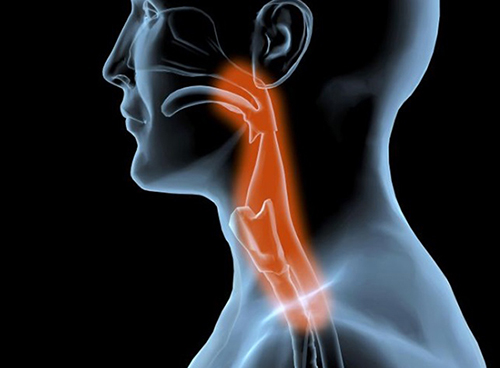

목디스크의 증상은 여러종류가 있으며 환자마다 그 증상이 같지않게 생겨날수 있습니다. 최고 흔한 증상으로는 목의 통증입니다. 목의 통증은 목 뒤쪽, 어깨, 팔, 손까지 뻗쳐서 일어날 수 있습니다. 거기에다가, 저림, 마비, 감각 이상, 손발의 힘 저하 등의 증상이 발생할 수 있습니다.

많은 종류의 사고 및 스포츠 관련 부상으로 인한 목 외상은 목 디스크에 과격한 손상을 유발할 수 있습니다. 또한 목을 갑작스럽고 강하게 움직이면 디스크가 찢어지거나 탈출할 수 있기에 이러한 부상을 입지 않을수 있게 조심하는 것이 필요합니다.

우리의 목은 인체에서 무척 요긴한 역할을 합니다. 머리를 지지하여 돕고, 머리를 움직여 시야를 확보하는 역할을 히며, 척추의 시작 부분으로서 척추를 지켜주고, 척추를 통해 뇌와 인체의 다른 부분으로 신경을 보급하는 역할을 합니다.